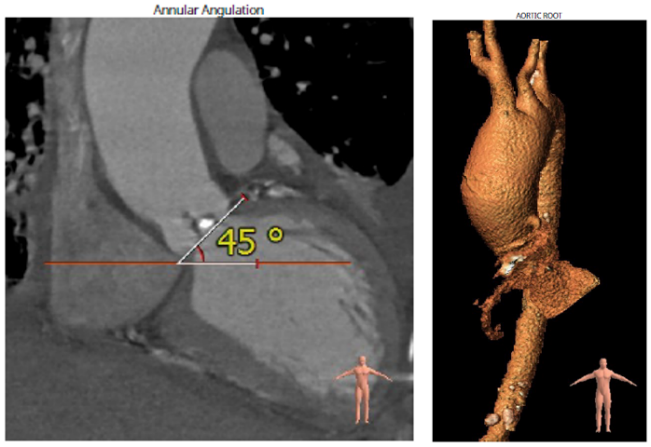

1、Type0型二叶式主动脉瓣,高龄,心功能差;

3、瓣环形态特异,开口受限,瓣叶钙化,左右冠脉走形特异伴左冠开口偏低。

CT分析:

根据测得的瓣环直径,结合患者二叶式主动脉瓣,瓣叶见钙化,以及畸形的有效开口,术中决定采用Evolut PRO 23mm瓣膜。递送系统顺利过弓跨瓣,球囊预扩后目标深度开始释放,得益于可回收设计,术中再回收进行一次位置调整,最终目标位完美释放,瓣膜立即工作,展开形态良好,无冠脉阻挡,无传导阻滞发生,术后压差<10mmHg,血流动力学稳定,手术圆满成功。